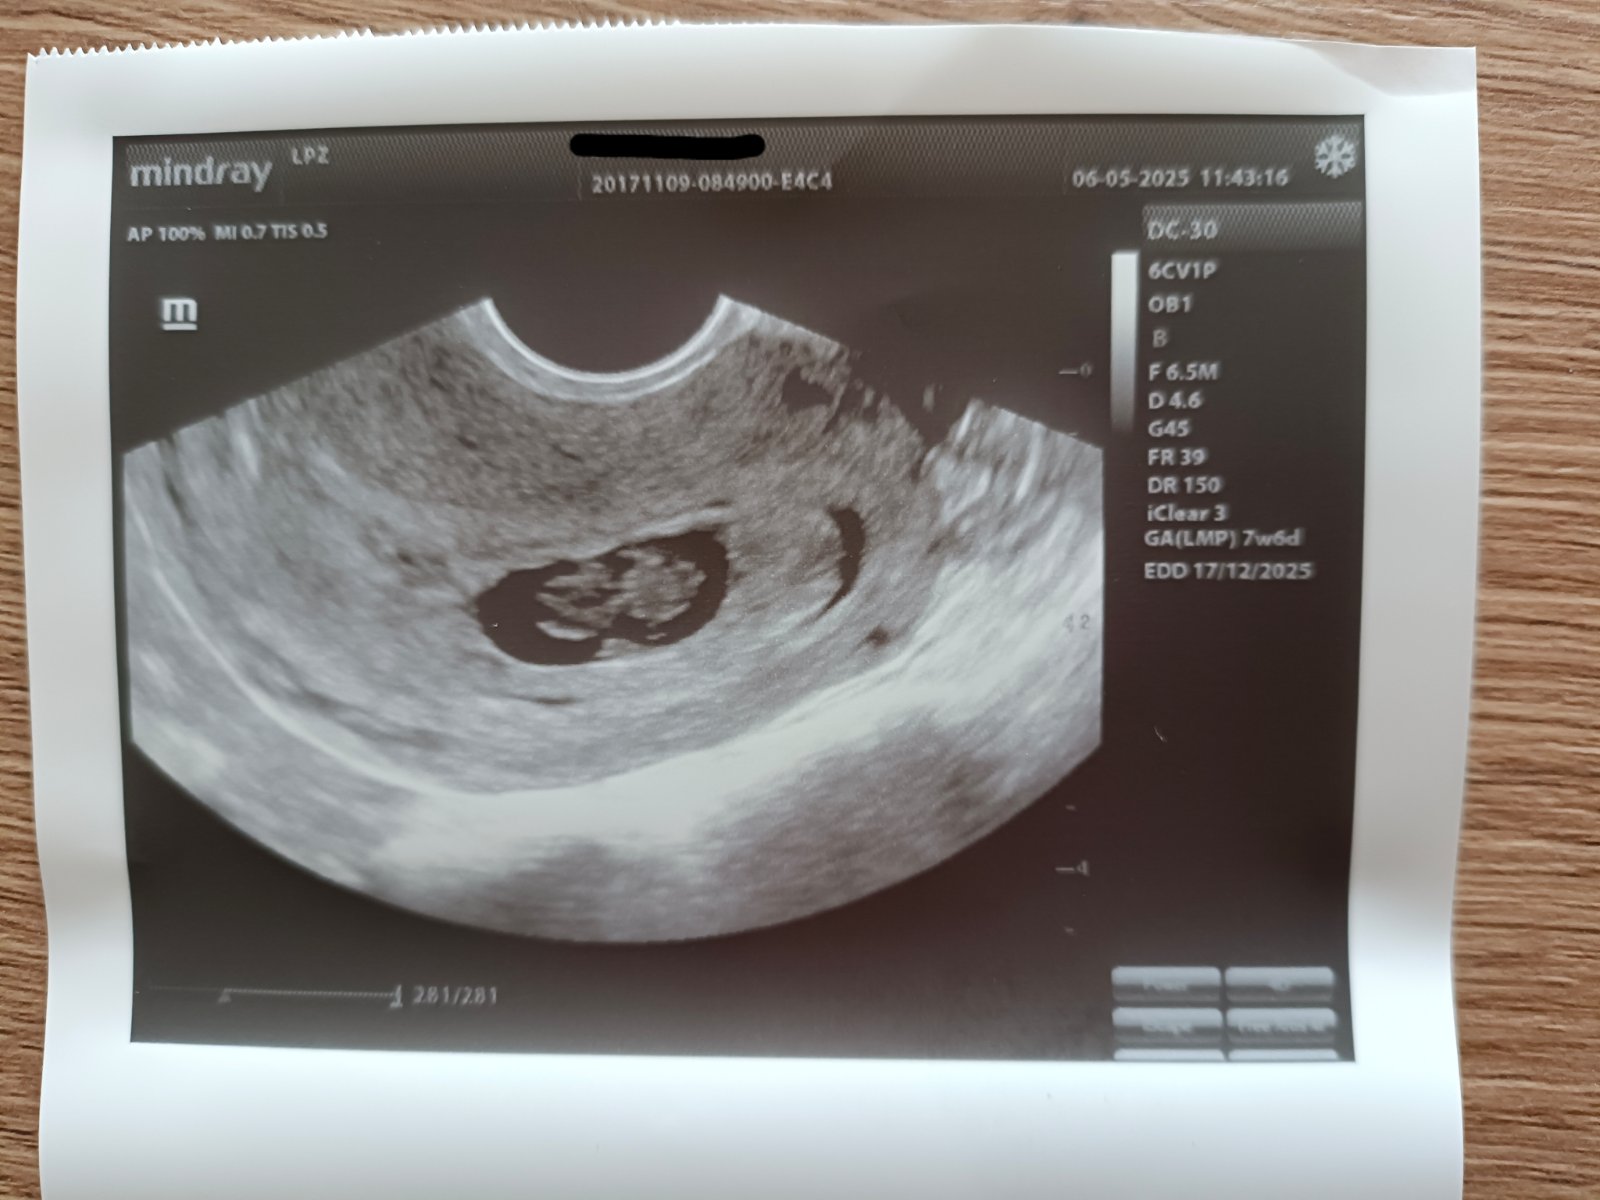

Ahojte, tak sa hlásim po 2. kontrole, podľa PMS som 7+6tt a podľa uzv 7+5tt, asi to aj sedí, keďže uhniezdenie bolo o čosi neskôr 🙂 doktorka videla všetky končatiny a že to vyzerá, že ide všetko ako má ... Ďalšia kontrola, kedy dostanem aj tehotenský preukaz, je 21.5. a zajtra na krv a moč do labáku, plus sa mám objednať na prvotrimestrálny screening 😊